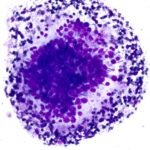

Slide Quality

Our propriety monolayer preparation ensures minimal cellular overlap, giving a clear view of cellular features. Every slide looks expertly done—even without the expertise.